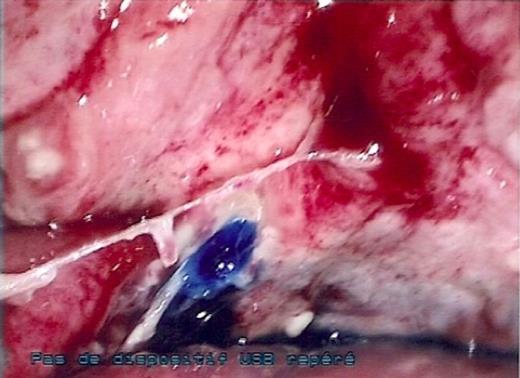

Due to systemic infection with no sign of improvement, a laparoscopic surgical exploration was decided. The patient underwent laparoscopic surgery with three trocars, a 10 mm umbilical trocar and two 5 mm trocars, one in each iliac fossa. Abdominal exploration found bowel loops of the ileum clustered at the bladder and liquid in the peritoneal cavity. Despite adhesiolysis, the perforation was not visualized. Methylene blue dye was injected through the Foley catheter and it highlighted a 1 cm perforation in the bladder dome (Figure 2) with no other macroscopic lesions. The perforated part was sutured with interrupted vicryl in one layer. A methylene blue dye test was performed and excluded a leak. Abdominal cavity lavage with 0.9 % saline was performed. A suction drain was placed into the pouch of Douglas.